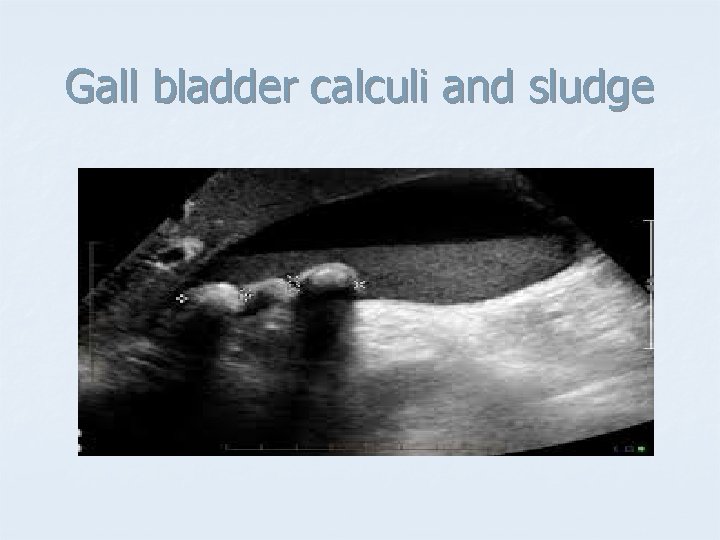

Gall bladder calculi and sludge